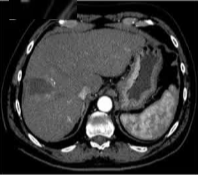

69 岁的男性患者,患有丙型肝炎相关肝硬化,其肝脏增强扫描(S8)中可见一个 22 mm 肝细胞癌结节。